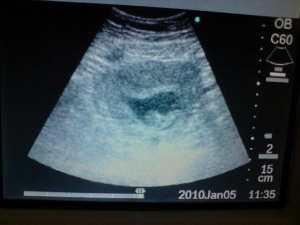

The 2nd February eventually arrived and off we went for another scan, yet again I was full of cold but otherwise all was fine, the nosebleeds had eased off and thankfully I wasn’t anaemic. Scan went fine; baby definitely a baby now and continued to measure fine.

Teresals3rdscan Pics.JPG